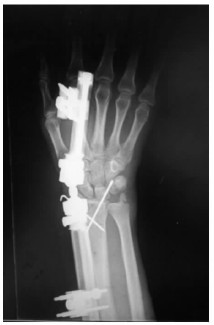

1.2 治疗方法急诊予以常规患侧腕关节正侧位X线片,必要时CT三维重建(图 1、2)。均采用臂丛麻醉,仰卧位,常规消毒铺巾,止血带止血。开放者直视下克氏针穿针固定,闭合骨折由助手牵引,手法复位纠正侧方移位,成角及短缩畸形,术中X线透视,骨折块或关节面复位不满意可借助克氏针撬拨复位或有限切开复位,复位满意后用多枚克氏针交叉固定。克氏针以刚穿出骨皮质为宜,以增加牢度,克氏针尾部折弯留于皮外,骨折初步复位后予以安装动力型外固定架,选择超关节外固定架,先于第二掌骨背外侧作2个0.5 cm切口,间距以外固定架钉夹为准,平行植入2枚2.5 mm支架螺钉,在距桡骨骨折线4~6 cm桡骨上置入2枚支架螺钉,安装并调整外固定架,保证远端球形活动关节位于桡腕关节水平线上,利于早期功能锻炼,同时调整外固定架施以适当牵引力,保持腕关节轻度尺偏掌曲位并锁紧,直至透视满意。术后第2天开始手指伸屈曲能锻炼,术后第1天,4周,6周、8周及3个月复查X线片(图 3、4),4周松外固定架锁紧装置开始功能锻炼,4~6周拔除克氏针,6~8周拆除外固定架。

| 图 3 术后4周正位片 |